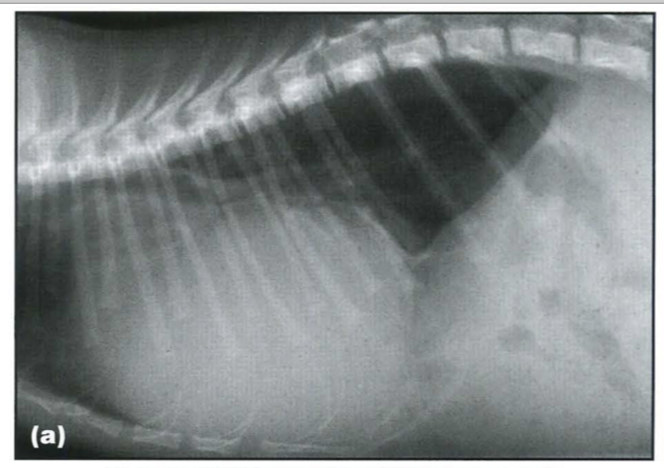

Peritoneopericardial diaphragmatic hernia (PPDH) is the most common diaphragmatic hernia in dogs and cats. It is due to an embryological fusion defect in the ventral diaphragm, leading to a communication between the pericardial and the peritoneal cavities. PPDHs are often associated with sternal or cardiac defects. The liver is the most frequently herniated organ, and may be associated with gallbladder, stomach, small intestine or omental herniation.

Clinical signs depend on the organs herniated and the size of the defect, and include respiratory, cardiovascular and gastrointestinal disorders. Auscultation may reveal muffled heart sounds or borborygmy over the cardiac area. Sudden onset of clinical signs may arise secondary to strangulation of a herniated organ. Most frequently no clinical signs are present and a PPDH is found incidentally.

Radiographic findings include: